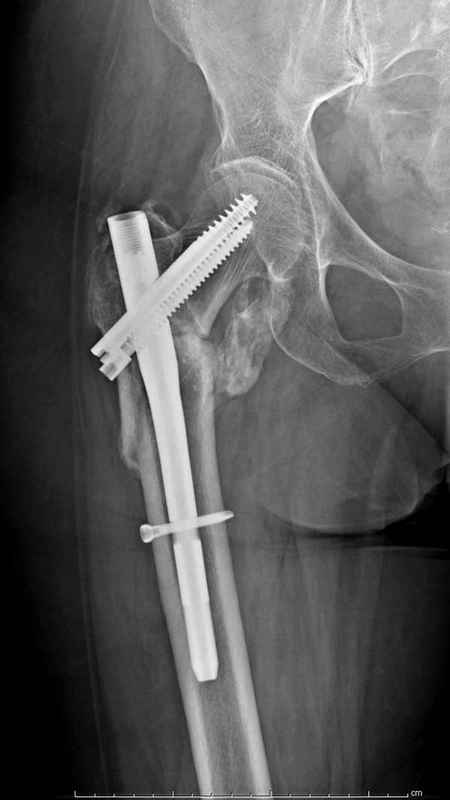

Здесь пара случаев фиксации похожих переломов:

первый высокоэнергетическая травма 36 лет

Djoldas Kuldjanov, M.D.